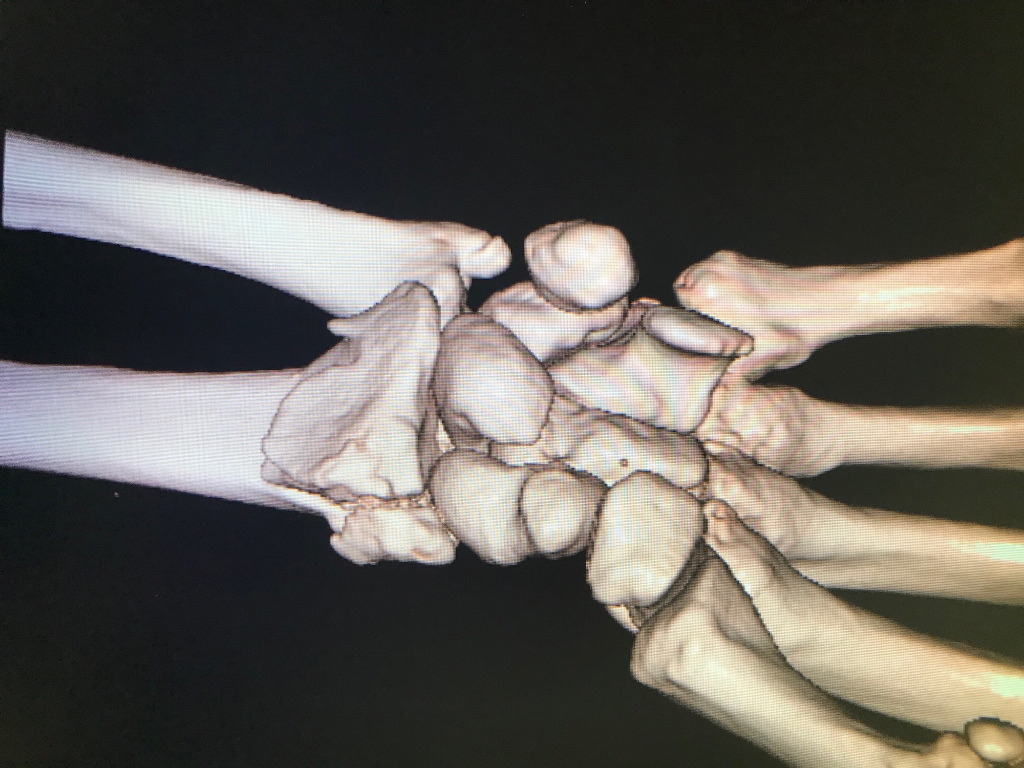

L'examen physique et les radiographies sont essentiels pour le diagnostic précis de ces fractures et pour orienter le traitement. Les radiographies standards peuvent être complétées par un examen scanner si la fracture est intra-articulaire.

Le diagnostic de fracture du scaphoïde se fait à la radiographie standard du poignet. Lors des fractures strictement non déplacée, il est parfois difficile de voir le trait de fracture, et on fait le diagnostic en réalisant un scanner.